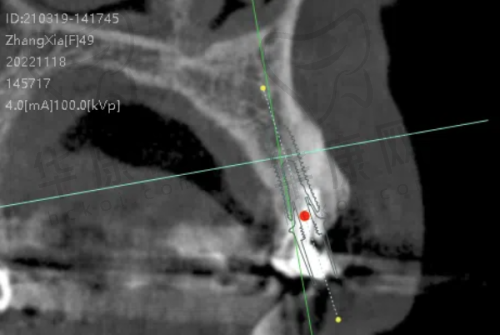

陈晓莉医生是厦门登特口腔医院口腔种植技术院长,从事口腔医疗工作已有20多年,经验多,技术不错。她经常到国外做考察和调研,能够了解全新的口腔医学治疗理念和方法。在瑞士士卓曼ITI种植牙项目上,她擅长做即刻种植牙、微创即刻种植牙、全口/半口牙颌种植等。曾有78岁的王奶奶因骨量不足被多家医院拒绝,陈晓莉医生为其定制穿翼板种植方案,避开骨移植直接固定种植体,手术1小时搞定,老太太第二天就能喝粥了。这充分体现了陈晓莉医生在复杂种植牙手术方面的高超技术和丰富经验。